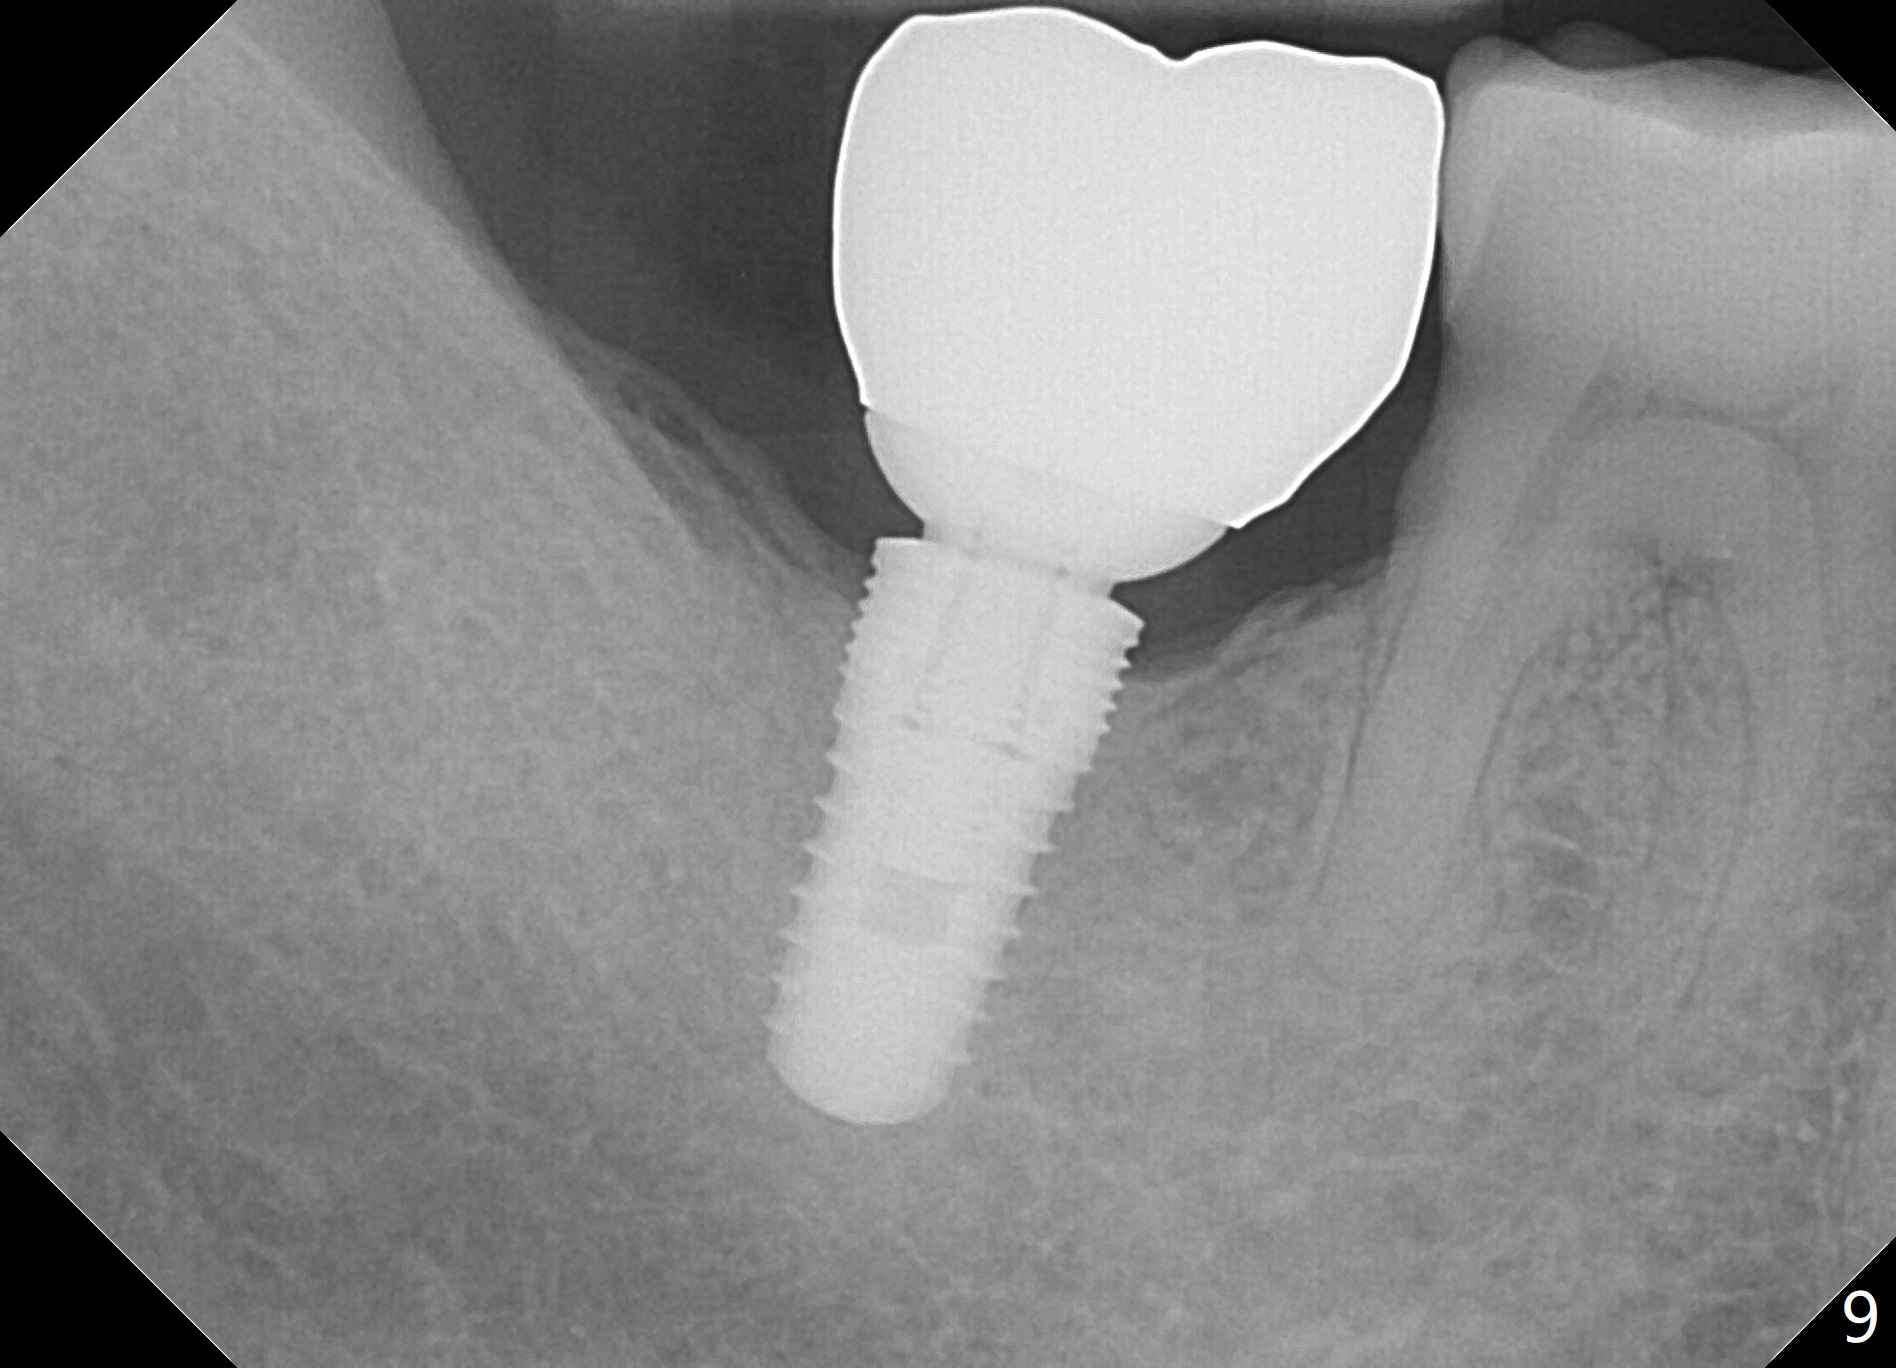

A 45-year-old man has diabetes. His oral hygiene is poor with both caries and chronic periodontitis. Nine years ago, the tooth #31 was non-salvageable (Fig.1). He does not accept treatment readily, especially extraction. At that time, the bone height is 20 mm.

There appears to be bone loss coronally 15 months postop (Fig.8). There is no bone loss 1 year post cementation (2 years 3 months postop, Fig.9). If the implant were longer, it might perforate the lingual (L) plate (Fig.10 (1.5 years post cementation)).